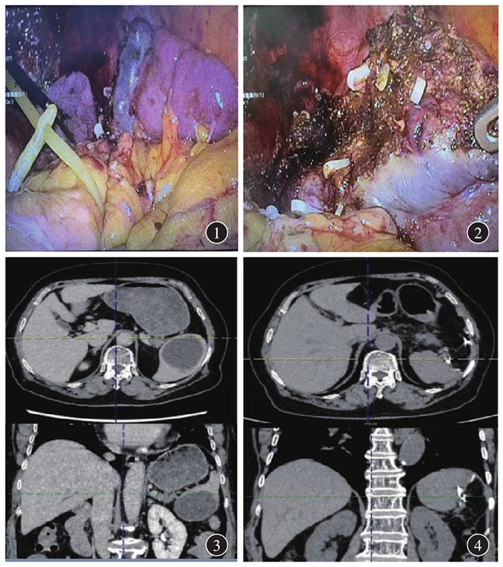

图4

术后3个月增强CT显示残余脾脏形态、血供正常